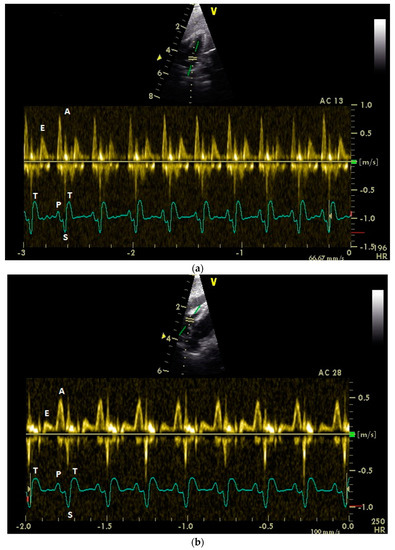

3.1. Diastolic Ventricular Filling Blood Flow Velocities in Conscious Racing Pigeons

3.2. Influence of Isoflurane Anesthesia on Diastolic Blood Flow Velocities

3.4. Examination of the Diastolic Blood Flow with Color Doppler Flow Imaging